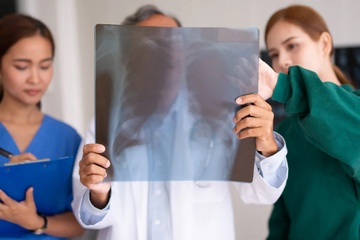

Loại ung thư đứng đầu về tỷ lệ tử vong

Ung thư phổi là nguyên nhân tử vong từ ung thư phổ biến nhất. Thế nhưng, những tín hiệu cảnh báo sớm như ho dai dẳng, khàn tiếng hay mệt mỏi lại dễ bị bỏ qua.